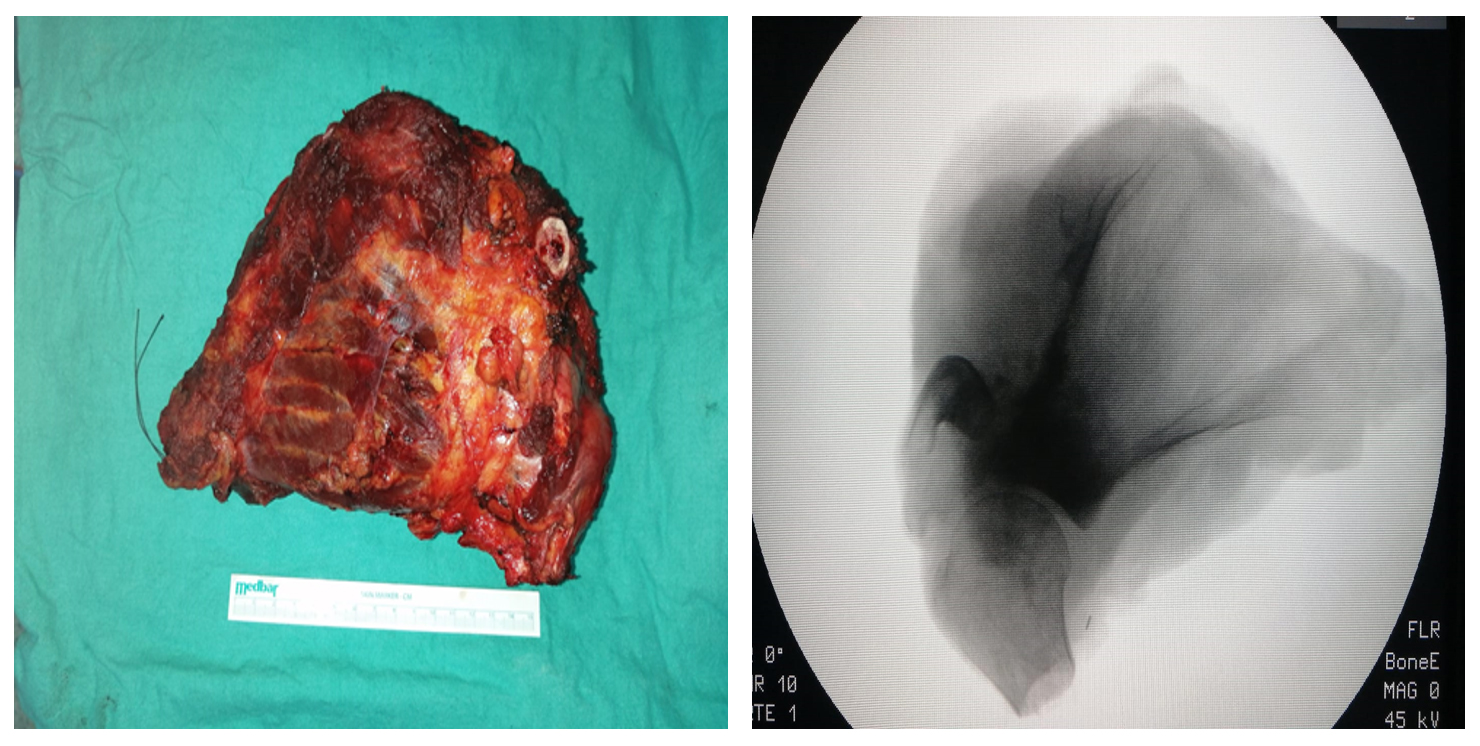

Ameliyat Esnası: Çıkarılan tümör dokusunun klinik ve skopi görüntüsü.